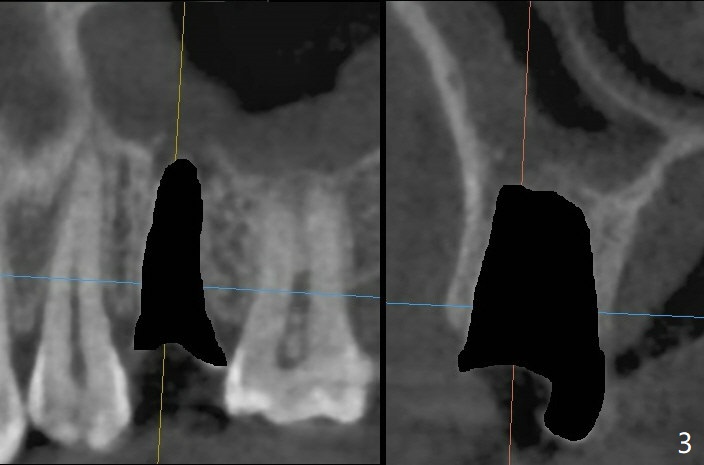

40岁女右上5树脂脱落,少许龋齿,近中边缘稍微龈下(图一:^),轻微叩痛(*)。经过商讨,她选择拔除植牙。CT检查显示上颌窦膜增厚(图二:*),为了减少术后上颌窦炎,第一,Z Pack(上呼吸道广谱抗菌素)和Medrol Dose Pack(激素)处方已开;第二,拔牙后(图三),将PRF膜推入上颌窦(图四:橘黄色),然后粘性骨块(红色圆圈);第三,植体长度刚好穿过窦底板(图五:11.5毫米)。Return to No Deviation 手术 No Neighboring Caries No Antibiotic 8, 10,30/31,19 Armaments 提升 Xin Wei, DDS, PhD, MS 1st edition 10/02/2020, last revision 03/28/2021